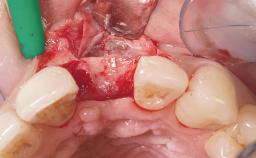

Late Flapless Placement of an Implant in a Maxillary Left Central Incisor Site

Anthony Sclar

A 39-year-old male patient presented with a chief complaint of discomfort and gingival discoloration around his maxillary left central incisor. He was in good general health and was a non-smoker. His past dental history was significant because of the traumatic fracture of tooth 21 in a sporting accident at age 13. Initial dental treatment included endodontic therapy and a full-coverage restoration. The patient became symptomatic 5 years later, when structural failure of the tooth resulted in the dislodgment of the crown. Endodontic retreatment, apical surgery, and post-and-core restoration were performed.